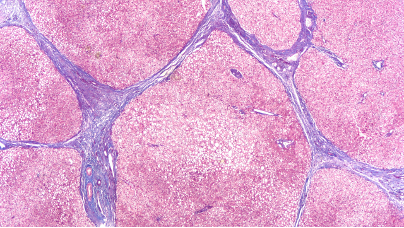

美国食品药品监督管理局(fda)已批准勃林格殷格翰公司的“贾赛迪”(奈瑞曼利斯特)片剂用于治疗特发性肺纤维化(ipf)。贾赛迪的获批使其成为近 10 年来首个获批用于治疗 ipf 的新疗法。由于 ipf 是一种罕见、严重且不断恶化的疾病,目前尚无治愈方法且治疗手段有限,此次获批标志着为那些患有该疾病的人提供支持的重要一步。

fda 是基于从两项 iii 期临床试验(纤布宁-特发性肺纤维化(ipf)试验和纤布宁-间质性肺病(ild)试验)收集的数据做出批准决定的。1 贾斯卡迪的疗效是在针对患有 ipf 的成年患者的两项随机、双盲、安慰剂对照试验中进行评估的。1 主要指标是用力肺活量(fvc)的绝对变化,即人在做最大深呼吸后所能用力呼出的最大空气量。1 结果表明,接受贾斯卡迪治疗的患者与接受安慰剂治疗的患者相比,fvc 下降幅度显著降低。1 贾斯卡迪的推荐剂量为每日口服 18 毫克,间隔 12 小时服用两次。1 贾斯卡迪的剂量可根据耐受情况减少至 9 毫克每日两次服用,但不适用于同时服用吡非尼酮的患者。1